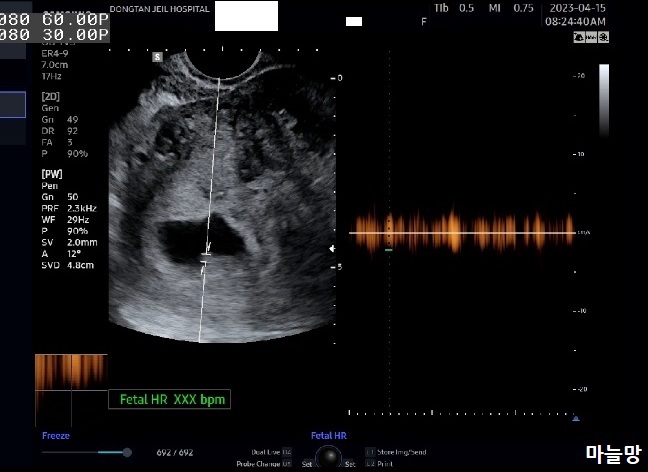

붉은 피가 후둥이 쪽에서 나온 것일 수도 있다는 의사쌤 말씀과 함께 6주 2일 차의 한참 작은 아기들의 심장소리도 들려주셨어요. 아직 아기들 주수가 작아서 심장소리는 마치 잘못 맞춰놓은 라디오 주파수 같았어요.

「취이이이이이익--------취이이익-----------」

선둥이는 심장 깜박임이 초음파 화면상으로도 선명하게 보였어요.

후둥이는 아직 너무 작아서 초음파 상으로도 심장소리 잡고 놓치고를 반복...!

오늘의 초음파 사진은 마미톡 캡처사진입니다.